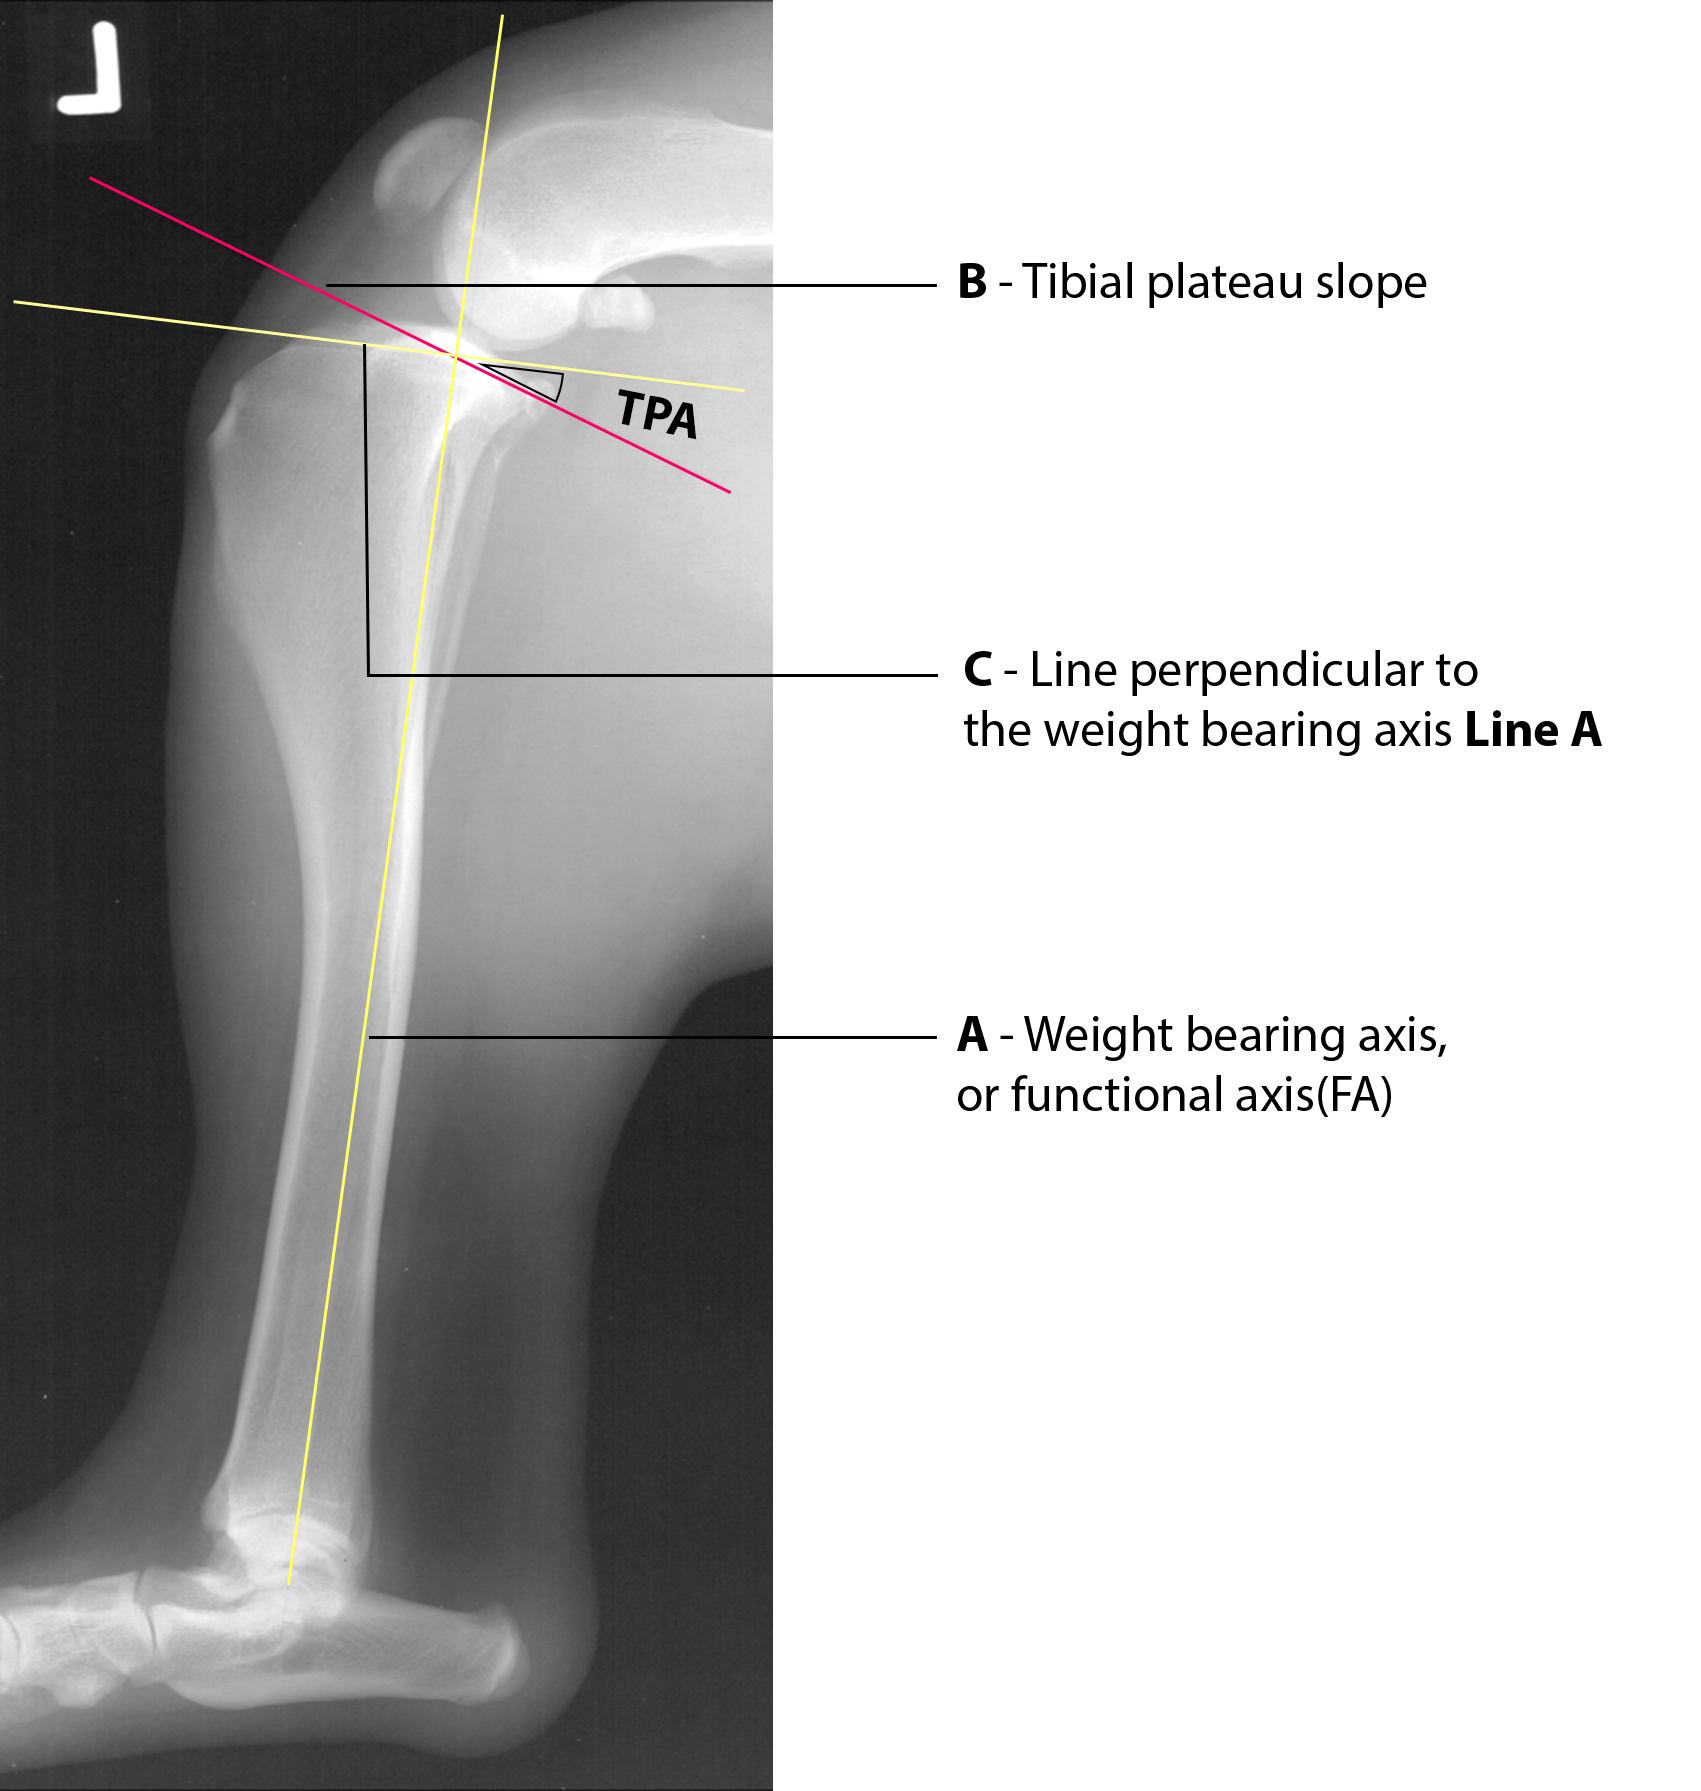

Determining the Tibial Plateau Angle (TPA)